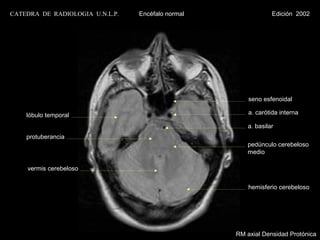

seno esfenoidal

lóbulo temporal                                    a. carótida interna

a. basilar

protuberancia

pedúnculo cerebeloso

medio

vermis cerebeloso

hemisferio cerebeloso

RM axial Densidad Protónica